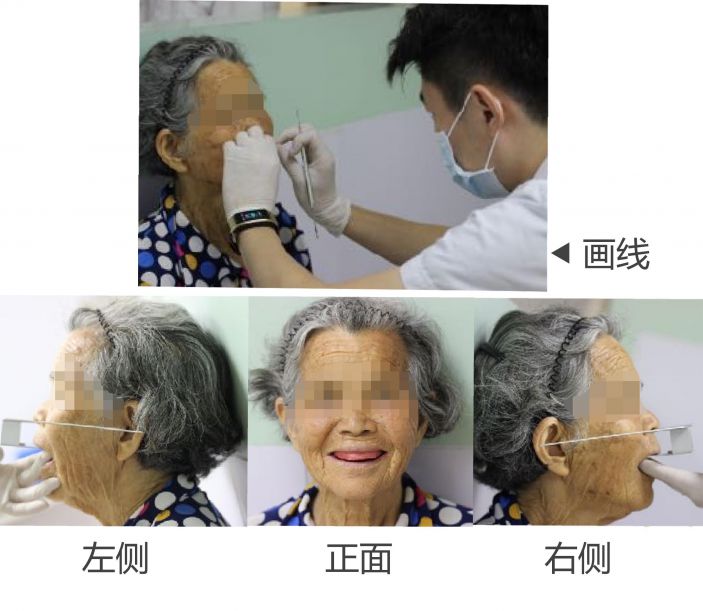

五、試排牙後行邊緣整塑

六、終印模

七、充膠、戴牙